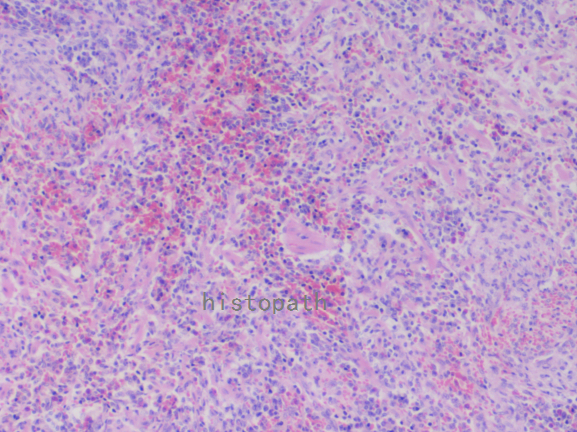

苏木精--伊红染色法(hematoxylin-eosin staining),简称HE染色法,石蜡切片技术里常用的染色法之一。苏木精染液为碱性,主要使细胞核内的染色质与胞质内的核酸着紫蓝色;伊红为酸性染料,主要使细胞质和细胞外基质中的成分着红色。HE染色法使组织学、胚胎学、病理学教学与科研中最基本、使用最广泛的技术方法。

染色结果:

细胞核呈蓝色,细胞质、肌肉、结缔组织、红细胞、嗜曙红颗粒呈不同程度的粉红色。钙盐、软骨基质和各种微生物也可染成蓝色或紫蓝色。核仁呈红色。着色情况不仅与组织或细胞的种类有关,也随其生活周期及病理变化而改变。质量优良的HE染色切片样本,细胞核与细胞质蓝红对比明显,胞核鲜明,核膜及核染色质颗粒均清晰可见。